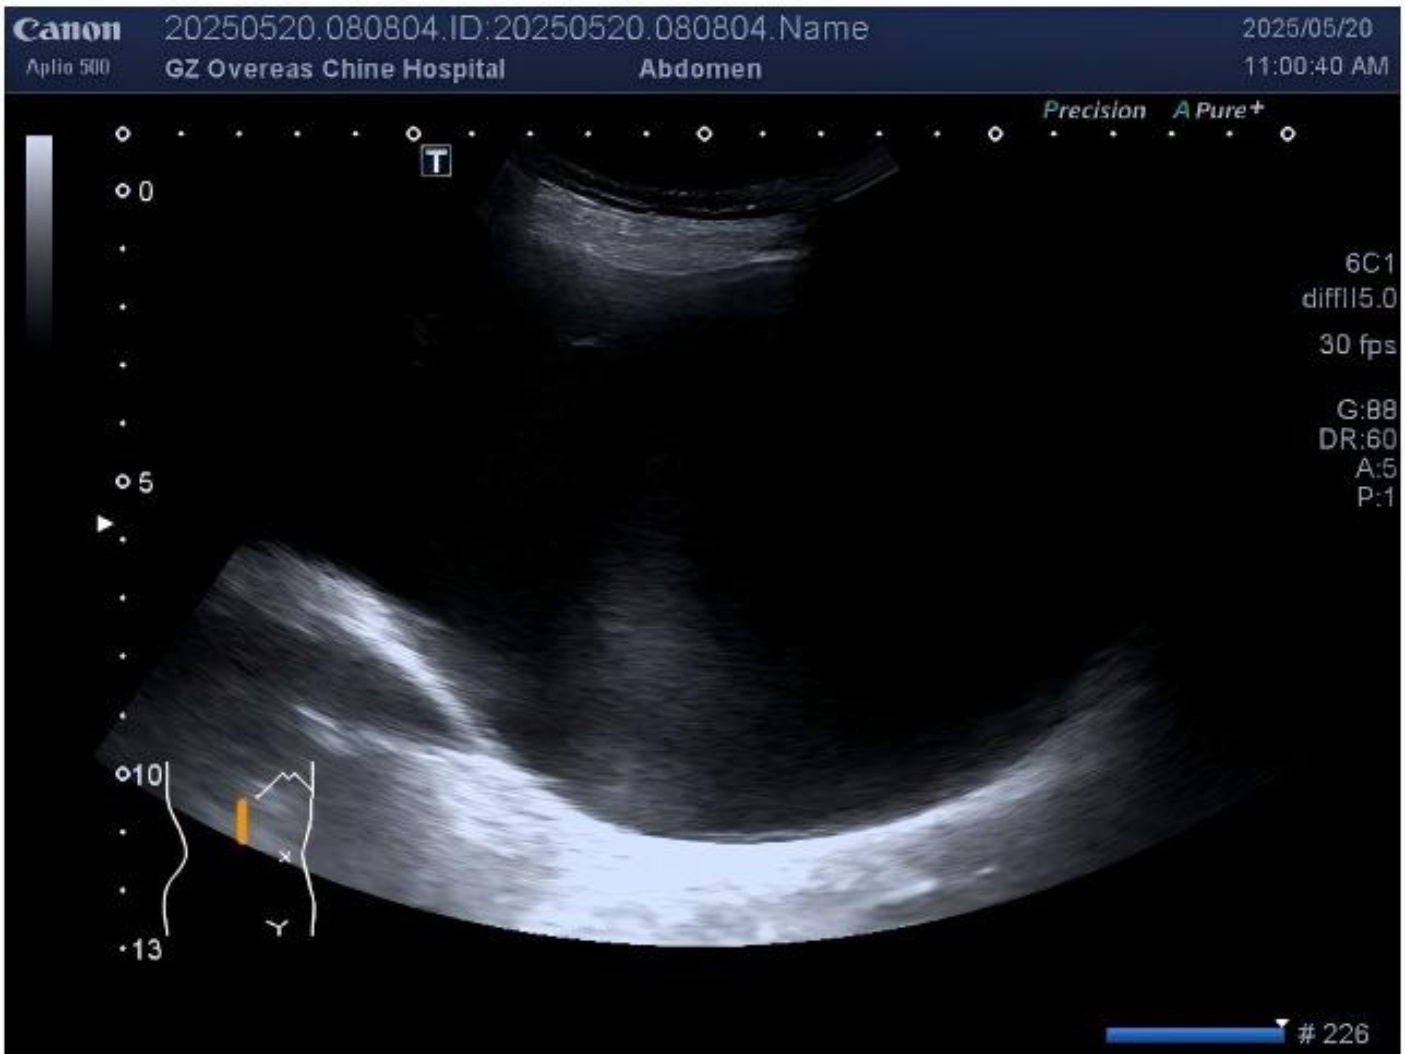

乳腺超声(2025-05-19):左乳见61 mm × 56 mm × 48 mm实性高回声肿块,边界欠清,形态不规则,内见多发无回声区及强回声点,血流信号丰富。左腋窝见多发低回声团(最大5 mm × 9 mm),皮髓质分界不清。提示:双腋窝副乳;左乳BI-RADS 4C类;右乳BI-RADS 1类(见图1(A)图1(B))。

(A) (B)

Figure 1. (A) Color Doppler ultrasonography of the left breast demonstrating prominent vascularity within a focal lesion; (B) Grayscale ultrasound of the left axillary region showing a round-shaped lymph node (LN) with a clear boundary but an indistinct corticomedullary differentiation

1. (A) 左侧乳腺彩色多普勒超声提示:乳腺内局灶性病变区域血流信号丰富;(B) 左侧腋窝区灰阶超声示:可见类圆形淋巴结(LN),边界清晰,皮髓质分界欠清